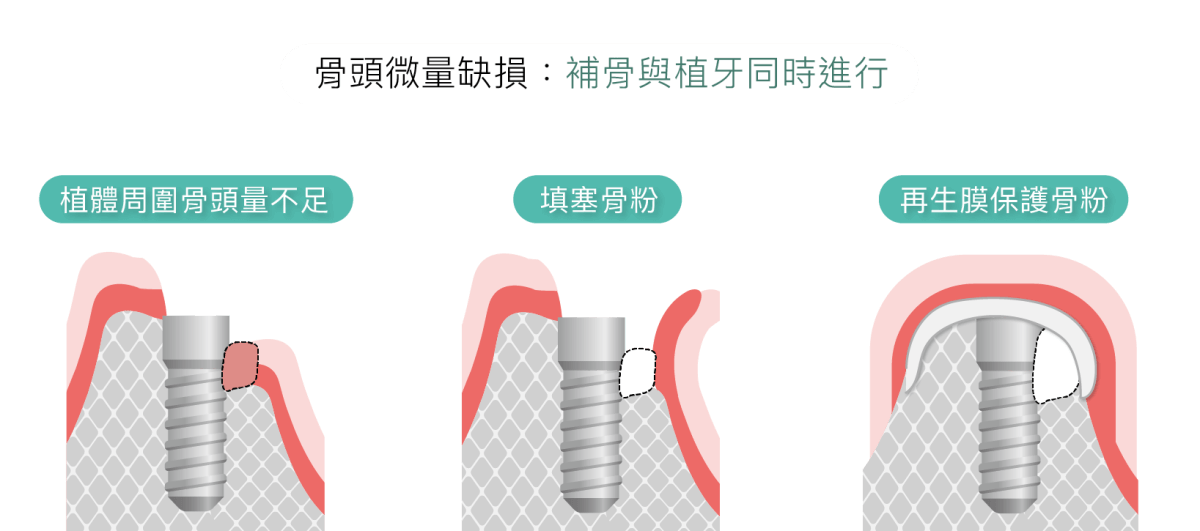

補骨粉後多久可以植牙,需視骨缺損的嚴重度而定。如骨頭條件介於中間,僅需再補上一點骨量,可以同時補骨加上植牙。

將人工骨粉或是骨塊,置入齒槽骨,補骨粉會建立一個架構,讓自體骨質細胞沿著生長。齒槽骨萎縮嚴重者,須等待骨頭新生完整,才能進行植牙;輕微者,植牙、補骨可同時進行。